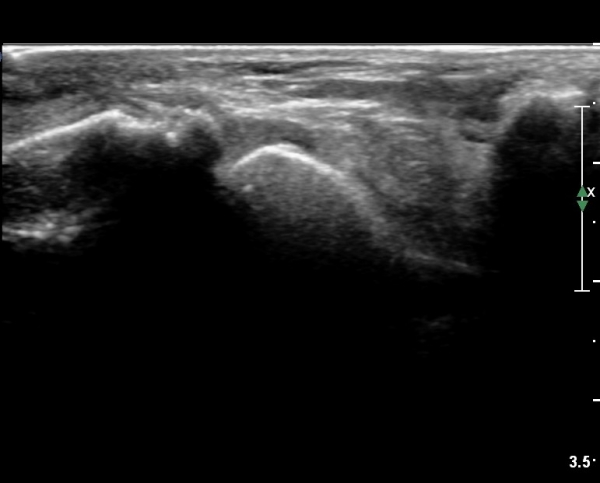

Àü¹æ ¸»´Ü °æ°ñºñ°ñÀδë Á¾´Ü¸é°Ë»ç¿¡¼­ ºñ°ñ ºÎÀ§ °æ°ñºñ°ñÀδëÀÇ Àú¿¡ÄÚºÎÁ¾ÀÌ °üÂûµÇ°í

ºÎÇϰ˻翡¼­ ºñ°ñÀÇ °úµµÇÑ ¿òÁ÷ÀÓÀÌ °üÂûµÈ´Ù(»çÁø 1, 2, µ¿¿µ»ó 1).